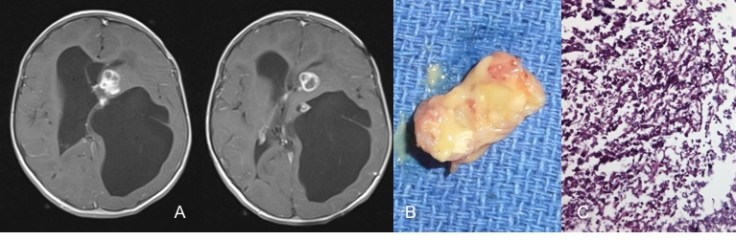

la plexectomie microchirurgicale

c’est une solution de dernier recours, en cas d’hydrocéphalie infectée et cloisonnée, c’est une geste chirurgical majeur mais qui peut être salutaire dans ces cas très difficiles.

l’infection méningée à Candida est redoutable en raison des cloisonnements et de la ténacité du germe, qui nécessite l’ablation de tous les cathéters et parfois la résection des foyers de granulome.